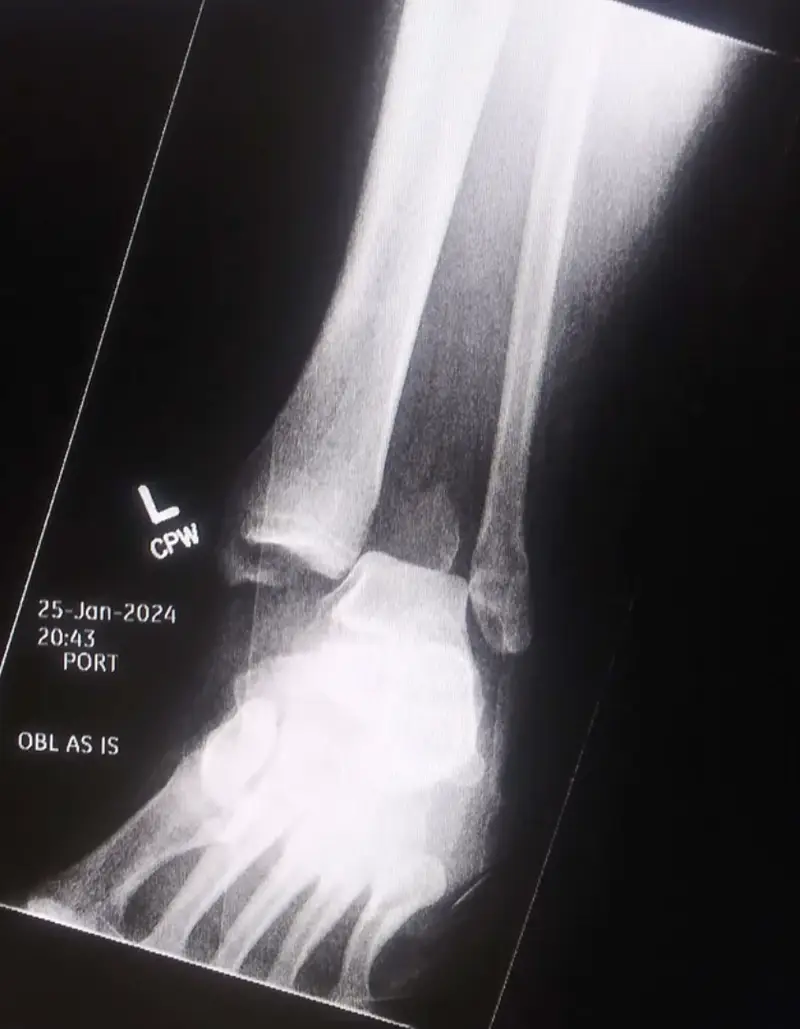

#2Aj ty tam vidíš čínske paličky? Má totiž zlomený členok